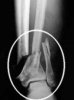

Never crashed or went down when this one happened. Just a little too fast coming down a hill climb and got off coarse.

Ankle.jpg